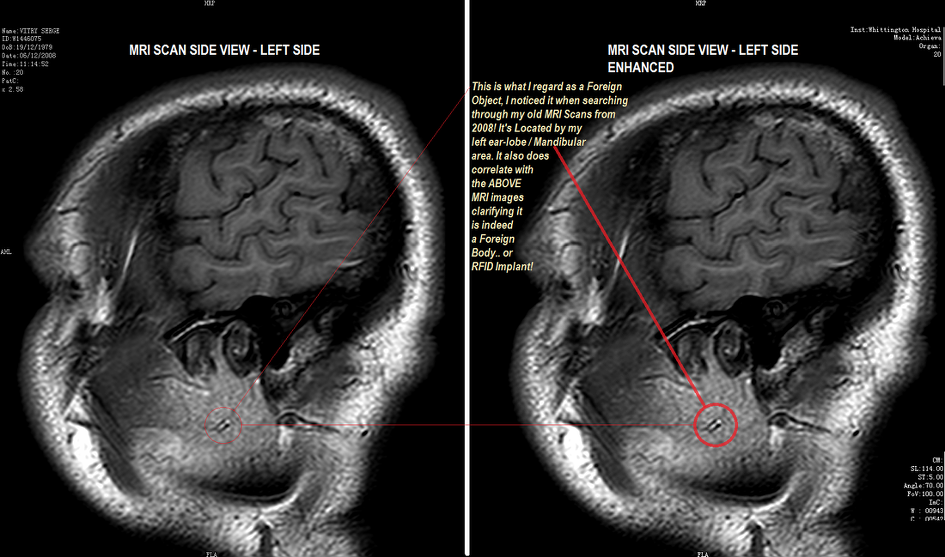

4. 마인드컨트롤 전자파 무기 피해자(TI: TARGETED INDIVIDUALS )들의 신체에 삽입된 칩

장비로 마이크로칩 검사하는 동영상

https://m.youtube.com/watch?feature=youtu.be&v=_rjvUZVhwoc

칩 제거하는 동영상입니다.

저는 미시건에서 온 레슬리 크로포드라고 합니다. 저는 Bio-technology에 대해서 말씀드리고자 합니다. 여기 제가 안과에서 진료받은 진단과 사진을 가지고 왔습니다.(사진을 보여줍니다.) 안과사진과 두뇌스캔사진을 보여줍니다. 그리고 악관절 임플란트사진을 역시 보여줍니다.